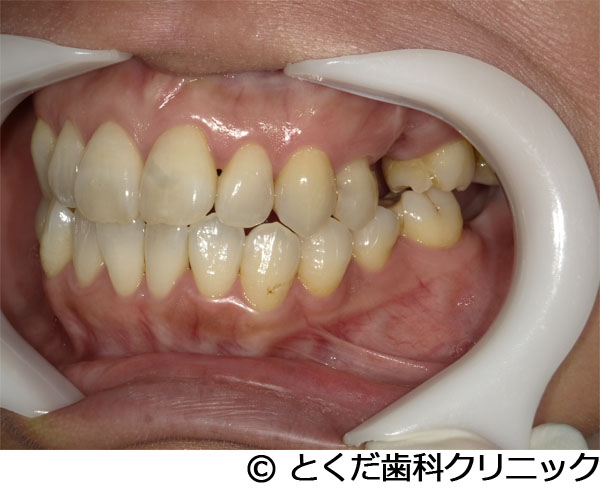

¡Ú¾ÉÎã1¡Ûº¸¾å3ÈÖ4È֤˴ؤ·¤Æ¤Ï¡¢¥¤¥ó¥×¥é¥ó¥È¤Î¼ê½ÑÅöÆü¤ËÈ´»õ¤ò¹Ô¤¤¡¢¥¤¥ó¥×¥é¥ó¥ÈËäÆþ¡¢ÅöÆü¤Ë²¾»õ¤ÎÁõÃå¡£±¦¾å5È֤˴ؤ·¤Æ¤Ï¡¢´û¸¹ü3mmÄøÅÙ¤·¤«¤Ê¤¤¥±¡¼¥¹¤Ë¥°¥é¥Õ¥È¥ì¥¹¥µ¥¤¥Ê¥¹¥ê¥Õ¥È¤ò»Ü¹Ô¡£¼ê½Ñ¸å¡¢4¥õ·î¤Ç¡¢ºÇ½ªÊäÄÖʪ¤Î3¥æ¥Ë¥Ã¥È¥¸¥ë¥³¥Ë¥¢¥Ö¥ê¥Ã¥¸¤Î¼£ÎŤò½ª¤¨¤¿¾ÉÎã

- º¸¾å3ÈÖ4È֤˴ؤ·¤Æ¤Ï¡¢¥¤¥ó¥×¥é¥ó¥È¤Î¼ê½ÑÅöÆü¤ËÈ´»õ¤ò¹Ô¤¤¡¢¥¤¥ó¥×¥é¥ó¥ÈËäÆþ¡¢ÅöÆü¤Ë²¾»õ¤ÎÁõÃå¡£±¦¾å5È֤˴ؤ·¤Æ¤Ï¡¢´û¸¹ü3mmÄøÅÙ¤·¤«¤Ê¤¤¥±¡¼¥¹¤Ë¥°¥é¥Õ¥È¥ì¥¹¥µ¥¤¥Ê¥¹¥ê¥Õ¥È¤ò»Ü¹Ô¡£¼ê½Ñ¸å¡¢4¥õ·î¤Ç¡¢ºÇ½ªÊäÄÖʪ¤Î3¥æ¥Ë¥Ã¥È¥¸¥ë¥³¥Ë¥¢¥Ö¥ê¥Ã¥¸¤Î¼£ÎŤò½ª¤¨¤¿¾ÉÎã

´µ¼ÔÍͤξɾõ

º¸¾å5ÈÖ¤ÎÇÓÇ¿¤È½ÅÅ٤λõ¤ÎưÍÉ¡¢½ÅÅ٤ιüµÛ¼ý º¸¾å3ÈÖ¡¢ÃæÄøÅ٤ιüµÛ¼ý¤ÈÃæÄøÅ٤λõ¤ÎưÍÉ¡¢¼«È¯ÄË

¼£ÎÅÊýË¡

º¸¾å3456¤Ë¥Ö¥ê¥Ã¥¸¼£ÎŤ¬¹Ô¤ï¤ì¤Æ¤¤¤¿¤¬¡¢º¸¾å5¤Î¹üµÛ¼ý¤ÈÇÓÇ¿¤òǧ¤á¤ë¤¿¤á¤ËÈ´»õ¤ò¹Ô¤Ã¤¿2¥õ·î¸å¤Ë´µ¼ÔÍͤϥ¤¥ó¥×¥é¥ó¥È¼£ÎŤò´õ˾¡£º¸¾å3¤Ë´Ø¤·¤Æ¤ÏưÍɤòǧ¤á¤Æ¤¤¤¿¤¿¤á¡¢Êݸ¤·¤Æ¤â¾ÍèŪ¤ÊÈ´»õ¤¬Í½ÁÛ¤µ¤ì¤¿¤¿¤áÈ´»õ¤ò¹Ô¤¤¡¢º¸¾å345¤Î3¥æ¥Ë¥Ã¥È¼°¥Ö¥ê¥Ã¥¸¤Î¥¤¥ó¥×¥é¥ó¥È¼£ÎŤò·×²è¡£½Ñ¸å¤Î¿³ÈþÌ̤ò¹Íθ¤·¤Æ¡¢º¸¾å3¤Î¥¤¥ó¥×¥é¥ó¥È¤Èº¸¾å4¤Î»Ã´Ö¥¤¥ó¥×¥é¥ó¥È¤òÍøÍѤ·¤¿²¾»õ¤òÆþ¤ì¤Æ¤¤¤Þ¤¹¡£º¸¾å3È֤λõÆùÂà½Ì¤òͽËɤ¹¤ë¤¿¤á¤Ë¡¢»õ¤Î°ìÉô¤ò²¹Â¸¤¹¤ë¥ë¡¼¥È¥á¥ó¥Ö¥ì¥ó¥Æ¥¯¥Ë¥Ã¥¯¤ò¹Ô¤Ã¤Æ¤¤¤Þ¤¹¡£º¸¾å5¤Ë´Ø¤·¤Æ¤Ï¡¢¾å³Ü¹ü¤¬¤«¤Ê¤êÇö¤«¤Ã¤¿¤¿¤á¡Ê´û¸¹ü3mmÄøÅÙ¡Ë¥°¥é¥Õ¥È¥ì¥¹¥µ¥¤¥Ê¥¹¥ê¥Õ¥È¤ò»Ü¹Ô¤·¤Æ¤¤¤Þ¤¹¡£ºÇ½ªÅª¤ÊÊäÄÖʪ¤Ï¥ª¡¼¥ë¥¸¥ë¥³¥Ë¥¢¤Î3¥æ¥Ë¥Ã¥È¥Ö¥ê¥Ã¥¸¤Ç¡¢À½ºî¤Ë´Ø¤·¤Æ¤Ï¡¢¥ª¡¼¥ë¥Ç¥¸¥¿¥ë¤Ç¹Ô¤Ã¤Æ¤¤¤Þ¤¹¡£

´µ¼ÔÍͤδõ˾Ä̤꿳ÈþÌ̤ò¹Íθ¤·¤Æ¡¢¸«¤¨¤ë¤È¤³¤í¤Ë»õ¤¬¤Ê¤¤¾õÂÖ¤¬¤Ê¤¯¼£ÎŤò½ª¤¨¤ë¤³¤È¤¬¤Ç¤¤Þ¤·¤¿¡£¤Þ¤¿¡¢º¸¾å5¤Ë´Ø¤·¤Æ¤Ï¥°¥é¥Õ¥È¥ì¥¹¥µ¥¤¥Ê¥¹¥ê¥Õ¥È¤ò»Ü¹Ô¤¹¤ë¤³¤È¤Ç¡¢½¾Íè¤Î¥µ¥¤¥Ê¥¹¥ê¥Õ¥È¤ò»Ü¹Ô¤·¤¿¾ì¹ç¤ÈÈæ³Ó¤·¤Æ¡¢6¡Á7¥õ·î°Ê¾åÁ᤯¼£ÎŤò½ª¤¨¤ë¤³¤È¤¬¤Ç¤¡¢º¸¾å3¤Ë´Ø¤·¤Æ¤Ï¡¢¥ë¡¼¥È¥á¥ó¥Ö¥ì¥ó¥Æ¥¯¥Ë¥Ã¥¯¤ò¹Ô¤¦¤³¤È¤Ç¡¢¼«Á³¤Ê¸«¤¿ÌܤλõÆù¤ÇºÇ½ªÊäÄÖʪ¤òÁõÃ夹¤ë¤³¤È¤¬¤Ç¤¤Þ¤·¤¿¡£½¾Íè¤ÎGBR¤ä¥µ¥¤¥Ê¥¹¥ê¥Õ¥È¤ò¹Ô¤ï¤Ê¤«¤Ã¤¿¤³¤È¤Ë¤è¤ê¡¢Ä㿯½±¤Ç¤Ê¤ª¤«¤Äû´ü´Ö¤Ç¼£ÎŤò½ª¤¨¤ë¤³¤È¤¬¤Ç¤¡¢¿³ÈþÌ̤ȵ¡Ç½Ì̤βóÉü¤ò¹Ô¤¦¤³¤È¤¬¤Ç¤¤Þ¤·¤¿¡£